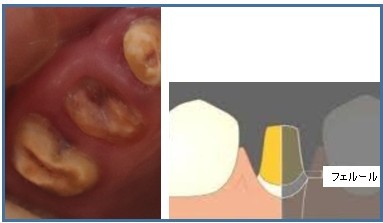

むし歯が進行し、歯ぐきの下(歯肉縁下)まで達してしまった歯は、周囲の組織の正常な構造が破壊されてしまいます(フェルールの喪失・根尖病巣の形成)。

この状態が改善できない場合、周囲の歯や骨に悪影響を及ぼすのを防ぐため、抜歯が必要となります。

フェルールの喪失とは?

フェルールとは、被せ物(クラウン)で覆われる健康な歯の部分のことです。

フェルールがある場合 → 歯にかかる力が分散され、歯の破折リスクが低くなる

フェルールがない場合 → 力が歯根の先端に集中しやすくなり、歯根破折のリスクが高まる

そのため、フェルールを確保できない歯は、抜歯の対象となることがあります。